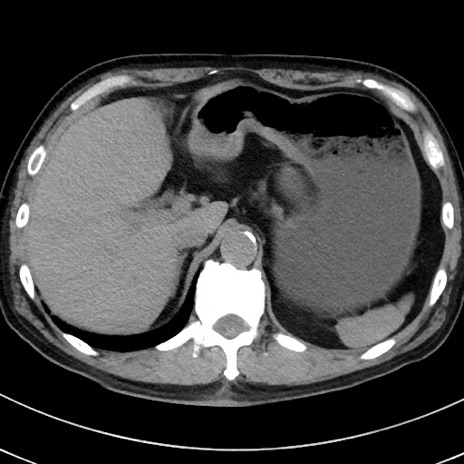

症例38(横断像)

【症例】70歳代 男性

【主訴】腹痛・嘔吐

【現病歴】昨晩より、嘔吐・腹痛あり。今朝になっても嘔吐あり。来院。

【既往歴】心臓バイパス手術、開腹胆摘、腸閉塞

【身体所見】BP 107/71mmHg、HR 116/min、腹部:平坦、軟、下腹部に軽度圧痛あり。反跳痛なし。

【データ】WBC 15100、CRP 0.32